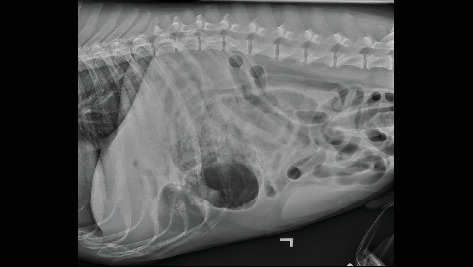

A 6-year-old, male neutered, German Shorthaired Pointer was evaluated for acute onset of emesis, tenesmus, and restlessness. Abdominal radiographs suggested gastrointestinal obstruction or torsion. An exploratory laparotomy revealed an omental-to-mesenteric adhesion causing entrapment and strangulation of a segment of the jejunum, along with several other adhesions. The patient had undergone two previous laparotomies, which likely contributed to the extensive adhesion formation found intraoperatively. While postsurgical adhesion formation is a known complication in both human and veterinary medicine, this case is notable for the unusual origin of the adhesions arising from the omentum. Furthermore, the severity of strangulation resulting from this adhesion required more extensive surgery and posed a higher risk for long-term gastrointestinal complications, such as short bowel syndrome.